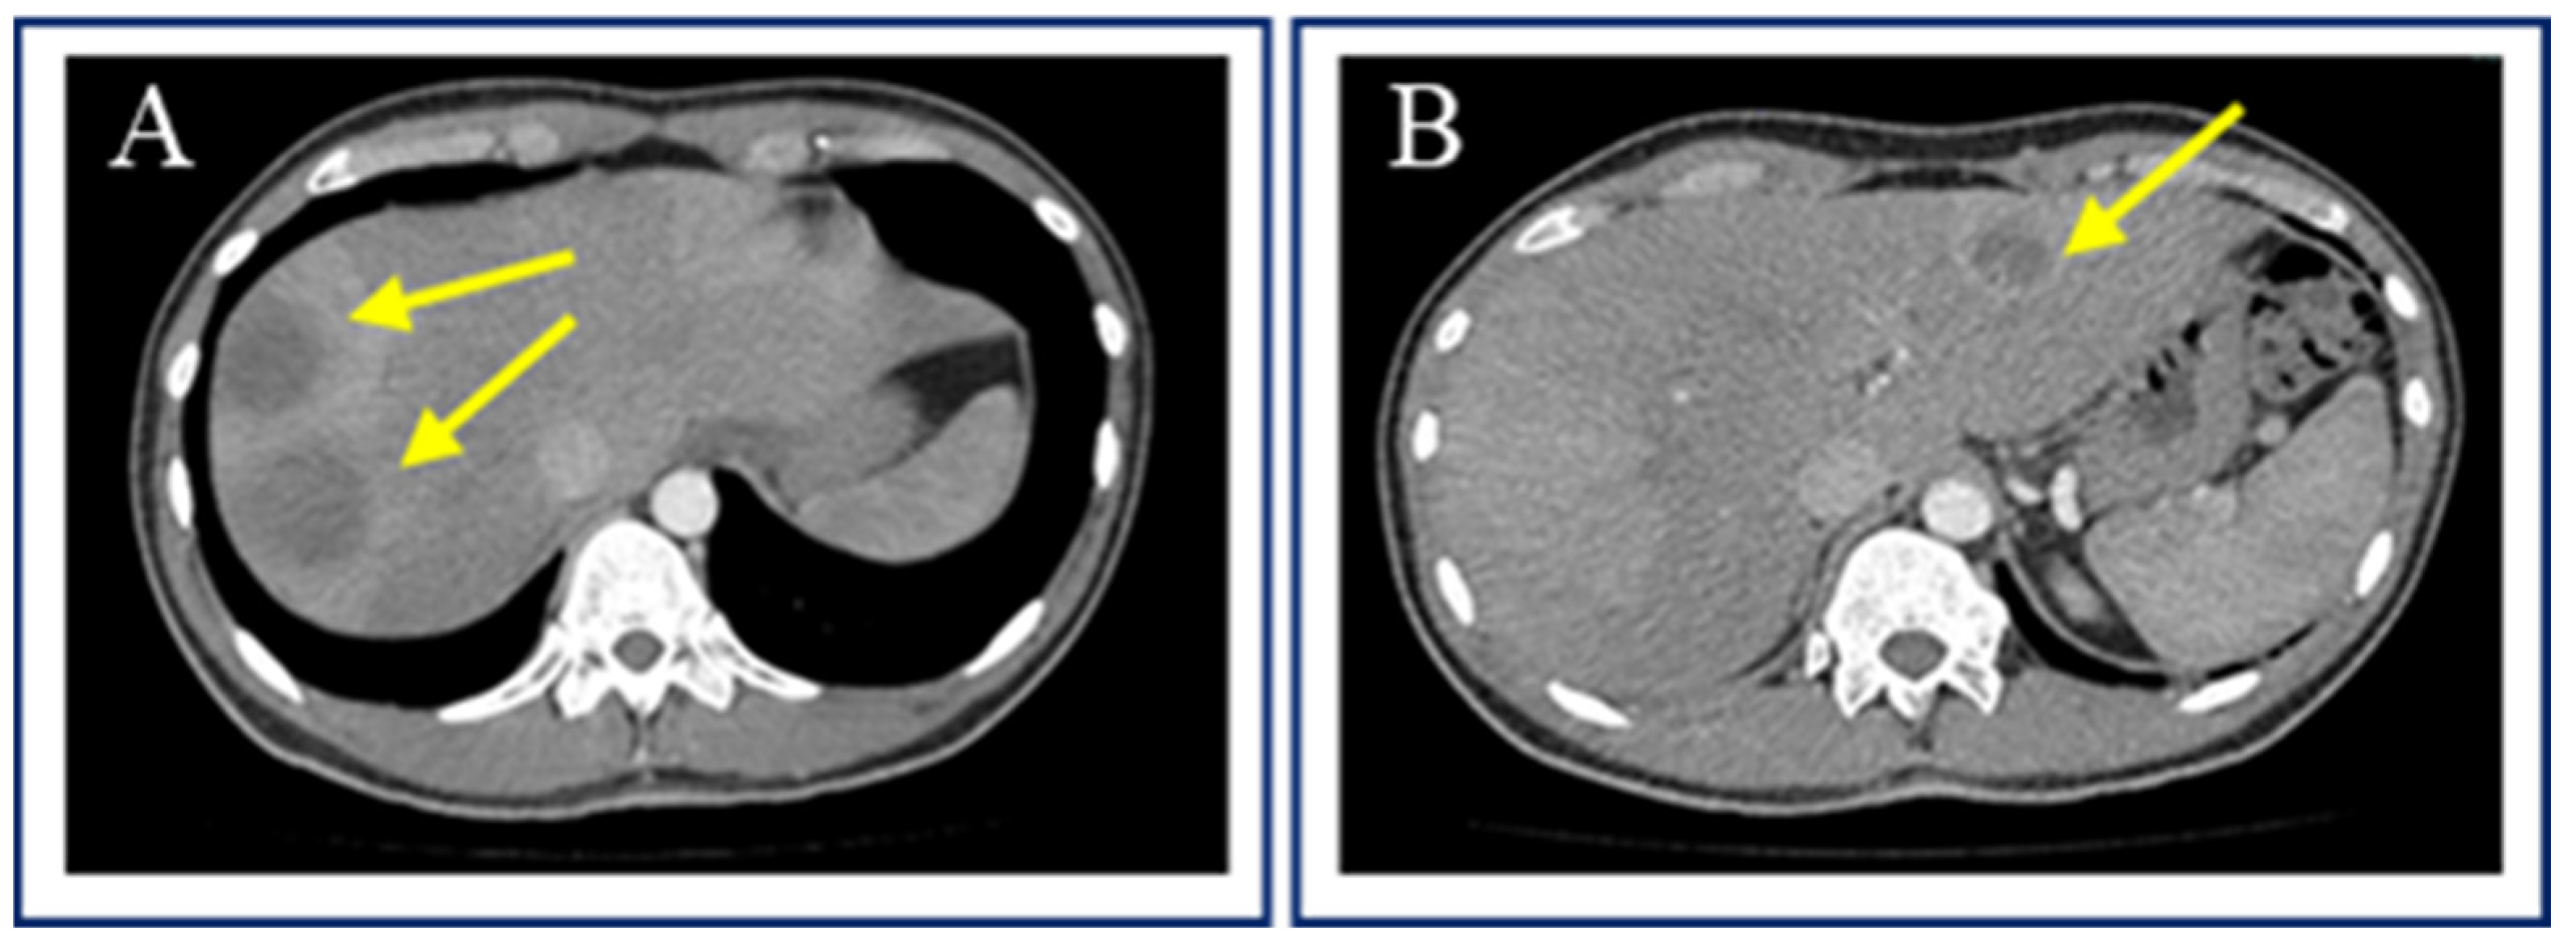

2. Case Report 1

3. Case Report 2